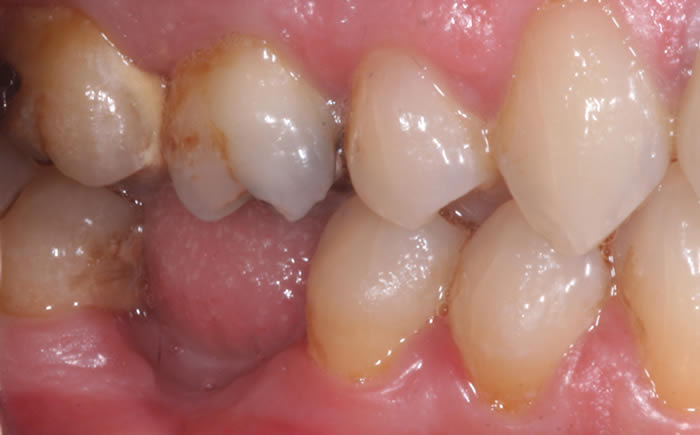

More back teeth replaced by dental implants

Case Three (2 images)

Case Four (4 images)

Case Five (4 images)

Case Six (8 images)

Case Seven (4 images)